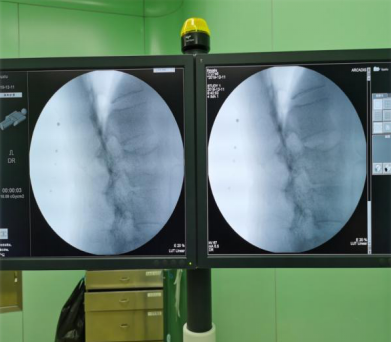

安装示踪器,调整机器人机械臂及标尺,行术中3D C型臂扫描

传送图像,规划腰2椎弓根钉钉道,沿机器人导向器,钻入导针,插入工作套管

C臂透视侧位钻头前端位于椎体前1/3,正位过椎体中线

此次机器人手术中,先由C型臂对患者进行三维影像扫描,图像被同步传输至手术机器人系统。医生在导航系统屏幕上设计好钉道,沿机器人导向器,钻入导针,插入工作套管。C臂透视侧位钻头前端位于椎体前1/3,插入球囊扩张器,注入骨水泥,透视可见椎体高度恢复满意,骨水泥分布良好。手术非常成功。